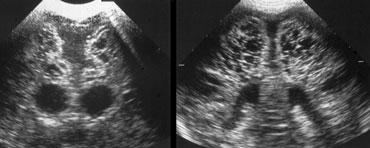

Xuất huyết nội sọ độ 2

Hình bên trái là xuất huyết nội sọ độ 2.

Trên mặt cắt đứng ngang, chỉ nhìn thấy khoang vách trong suốt.

Cả hai não thất bên đều chứa đầy máu, nhưng không có giãn não thất.

Hình bên trái là cùng bệnh nhân sau 3 ngày.

Các não thất giãn rộng và có hình ảnh hình thành cục máu đông.

Não úng thủy thứ phát xảy ra vài ngày sau xuất huyết độ 2 không nên bị nhầm lẫn với xuất huyết độ 3.